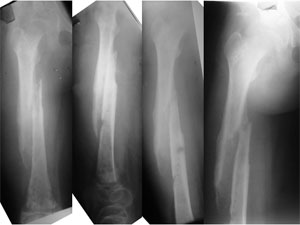

At the time of presentation to us the Infected bone had weakened and broken (pathological fracture). The disuse osteoporosis of the bone is evident in the lower portion of the femur. The salt and pepper kind of appearance on the x-rays can represent a confusing picture of some kind of bone tumor. |